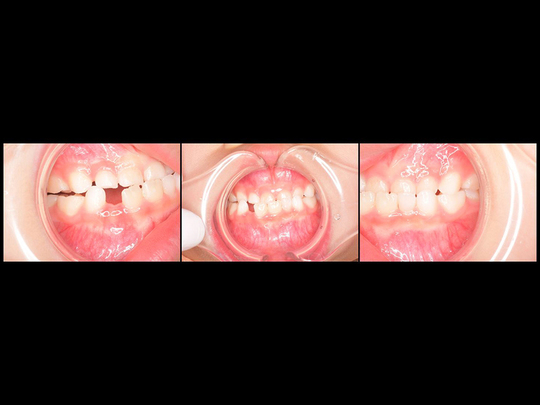

Aさん 開始時6歳 女性

矯正前

歯列矯正用咬合誘導装置(ムーシールド)  開始

矯正後

歯列矯正用咬合誘導装置(ムーシールド)  終了